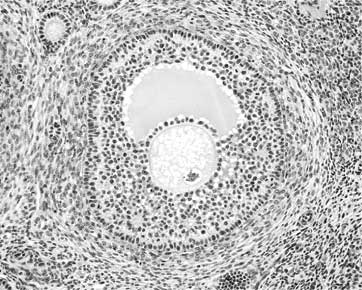

В яичниках находятся небольшие шаровидные образования, называемые «фолликулами». В каждом фолликуле содержится одна женская половая клетка, которую называют яйцевой клеткой или сокращенно – яйцеклеткой. Яйцеклетка окружена двумя соединительнотканными оболочками и слоем клеток, обеспечивающим ей не только защиту, но и доставку питательных веществ из жидкости, заполняющей фолликул. Клеточная оболочка яйцеклетки поэтично называется «лучистым венцом», а наружная соединительнотканная оболочка, находящаяся под лучистым венцом, называется «блестящей». Блеск оболочке придают содержащиеся в ней гликопротеины – белки, имеющие в составе молекулы сахаридные остатки.

Яйцеклетка не плавает в фолликуле, а располагается не выступе, который называется «яйценосным холмиком» или «яйценосным бугорком». Фолликул содержит клетки, способные вырабатывать гормоны. Это не просто хранилище яйцеклетки, а эндокринный орган.

Иллюстрация к книге — Твоя жизнь до рождения: тайны эволюции человека [i_009.jpg]

Фолликул